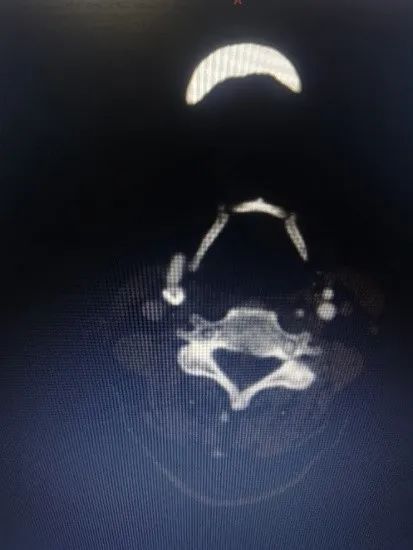

刘大爷这类患者颈动脉分叉位置高、病变斑块长,不适宜传统颈动脉内膜切除术,同时他主动脉有较多溃疡斑块,远端颈动脉扭曲,因此传统经股动脉入路颈动脉支架植入术(TFCAS)风险较大。经华山医院血管外科团队严格的术前评估后,团队决定应用TCAR技术规避CEA和TFCAS技术的不足,为刘大爷进行治疗。手术仅历时1小时便顺利完成,术后刘大爷恢复良好,脑缺血症状消失,于第三天顺利出院。

术前影像